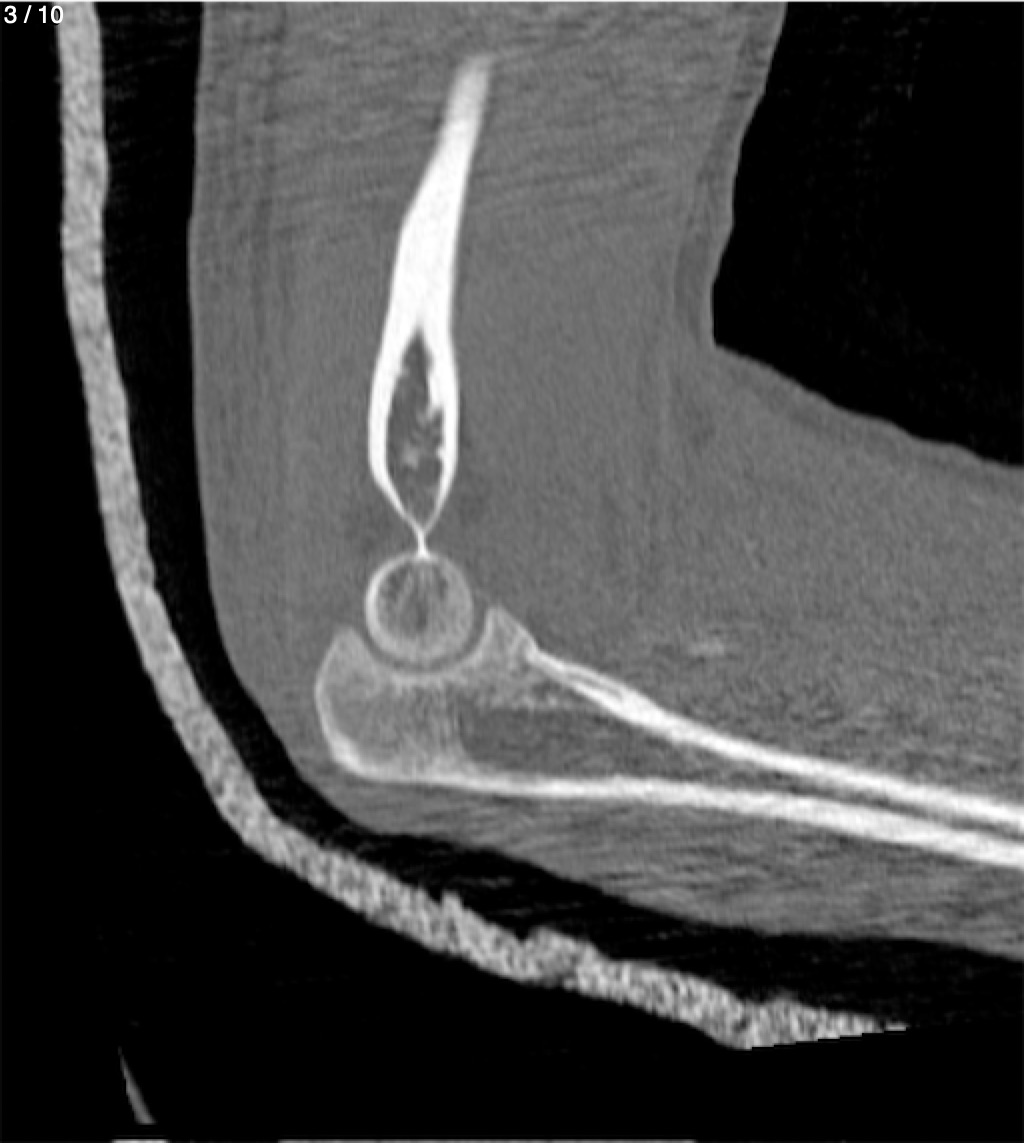

Antonio Dominguez Tino 21 A - Tac Codo Izq